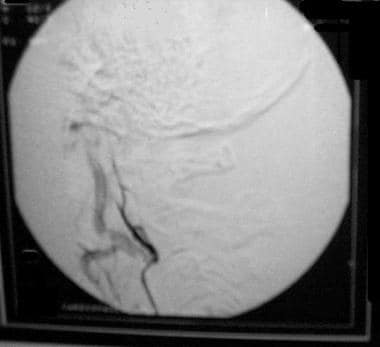

这张血管造影显示,在手术前,通过用聚乙烯醇颗粒栓塞右侧枕动脉,成功栓塞了小脑桥脑角脑膜瘤。